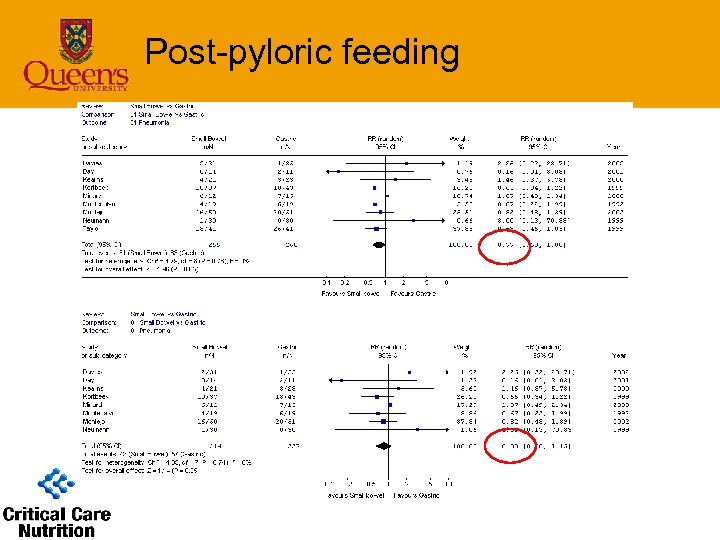

Post-pyloric feeding

Post-pyloric feeding